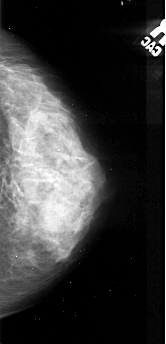

A_1045_1.LEFT_MLO

LEFT_MLO LINES 5206 PIXELS_PER_LINE 2311 BITS_PER_PIXEL 16 RESOLUTION 42 OVERLAY